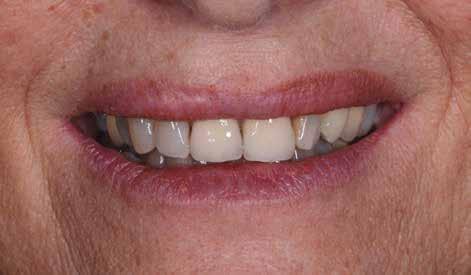

A 26 éves férfi páciens azzal a kéréssel kereste fel a rendelőnket, hogy a frontfogai esztétikusabb megjelenését szeretné elérni. A páciens jó általános egészségi állapottal rendelkezett, nem szenvedett allergiáktól és nem kellett rendszeresen gyógyszereket szednie. A páciens lehetőség szerint kerülte a fogai megmutatását. Rendkívül zavarónak találta a nagymetszői között, a középvonalnak megfelelően látható rést, a fogain látható kopási jeleket, valamint a fogai méretét is túl kicsinek találta. A szájüregi vizsgálat során megállapítottuk, hogy a nagymetsző fogai (11, 21) élharapásban vannak, valamint az alsó fogíven kismértékű torlódást észleltünk. A felső frontfogakon

(13-23) attrícióra utaló jeleket találtunk. A fogak kopása a nagymetszőfogaknak megfelelően volt a legkifejezettebb (1. ábra) . Az előbbiekben említett fogak (11, 21) ezen kívül némileg elfordultak, és jelentősebb méretű diasztéma volt köztük. A páciens Angle I.-osztályú állcsontrelációs helyzettel rendelkezett. A vizsgálat során feltűnt, hogy a páciens csak nagyon óvatosan mert mosolyogni (2. ábra)

A fogazat minimálinvazív módon készített héjakkal történő ellátásához a fogaknak olyan pozícióban kell lenniük, amely lehetővé teszi az esztétikai megjelenés additív eljárások alkalmazása mellett történő optimalizálását.1. ábra: Kiindulási állapot. A felső nagymetszőfogak élharapásban vannak. 2. ábra: Az orthodonciai kezelés megkezdése előtt készített intraorális felvétel. A páciens csak óvatosan mer mosolyogni. 3. és 4. ábra: Digitálisan megtervezett kezelés.

A kezelések második fázisában a pácienssel közösen non-prep/ minimálinvazív héjak készítése mellett döntöttünk (6. és 7. ábra).

A páciens teljesen elégedett volt a kezelések befejezését követően elért esztétikai végeredménnyel (9. ábra). A terápiás erőfeszítéseink eredményeinek köszönhetően újra képes felszabadultan nevetni és mosolyogni. A cikkben bemutatásra kerülő eset jól példázza a multidiszciplináris beavatkozások alkalmazásában rejlő előnyöket. A megfelelő sorrendben végzett orthodonciai és restauratív kezelésekkel lehetővé vált a páciens mosolyának minimálinvazív módszerekkel történő optimalizálása. A körültekintő tervezésnek köszönhetően nem került sor felesleges beavatkozások elvégzésére, és emiatt a kezelések befejezéséhez szükséges idő sem nyúlt a szükségesnél hosszabbra. Arra is felhívnánk a figyelmet, hogy a jól megszervezett, továbbá a lehető legkevesebb rendelési időt felhasználó kezelések – a beavatkozásokat végző fogorvosok számára is – rendkívül kedvezőek lehetnek.